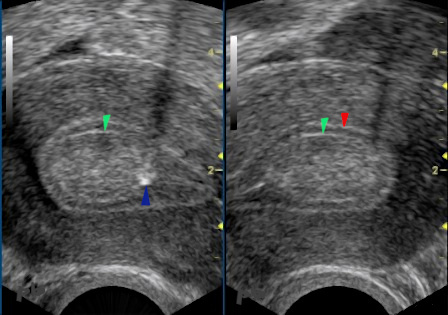

9 – Polype

(même patiente que 8)

Echographie par voie endovaginale. Coupes transversales avec doppler couleur.

Pédicule vasculaire (►). Il est très évocateur de polype, et fréquemment visualisé, mais pas toujours (en particulier chez les femmes ménopausées).

9 – Polyp

(Same patient as in image 8)

Endovaginal ultrasound. Transverse sections with color Doppler.

Vascular pedicle (►). This is highly suggestive of a polyp and is frequently visualized, though not always (particularly in postmenopausal women).